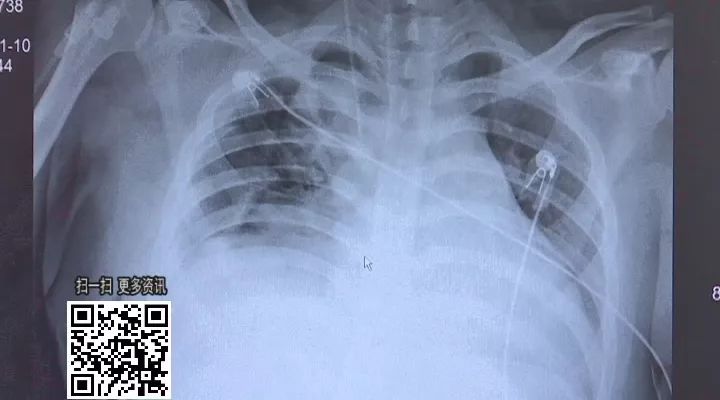

這張CT片是術后當天拍的,

從這里看胸腔已經(jīng)沒有積血,

心影也不是特別大,

整體來看沒有明顯的出血,

目前恢復非常好。